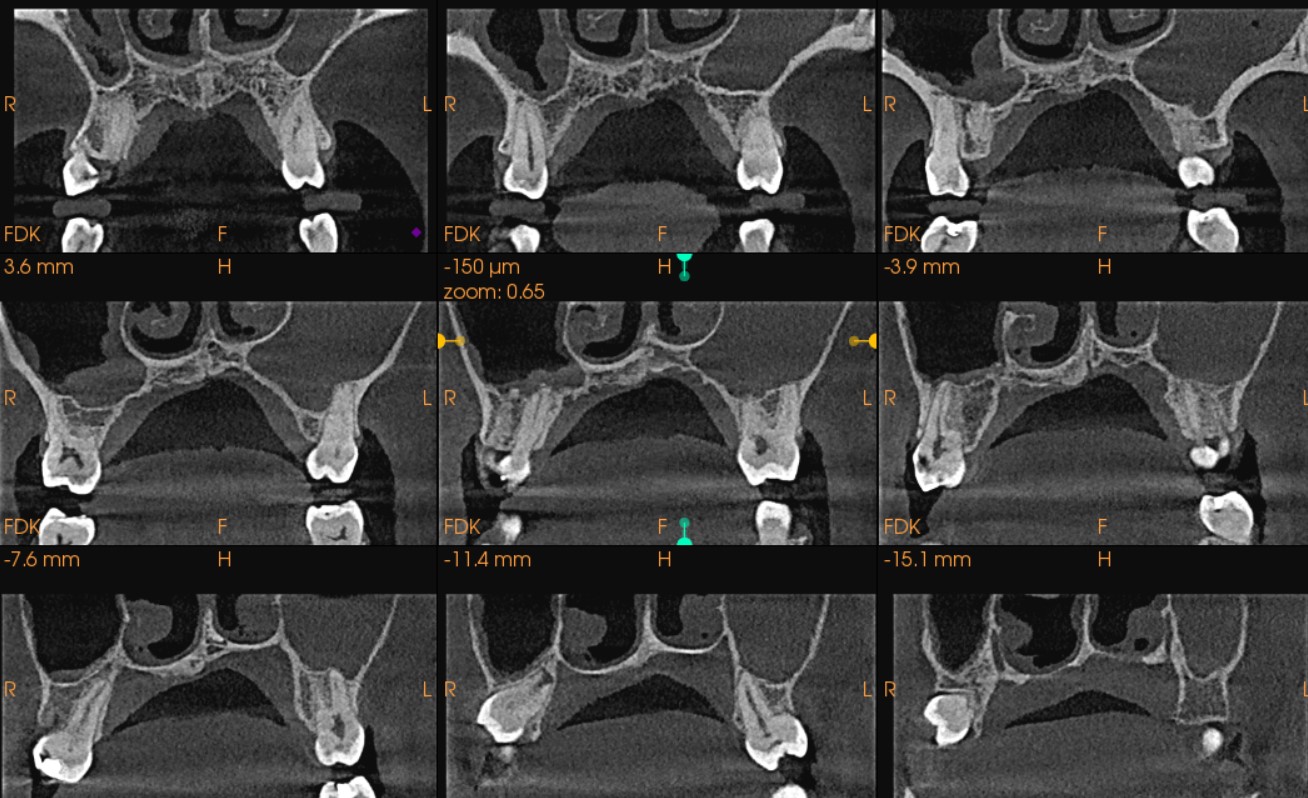

Atreves del recorrido de vista coronal y axial se pudo encontrar a seno maxilar derecho imágenes isodensas vinculante con engrosamiento de membrana sinusal, y la presencia de imagen isodensa que abarca la totalidad del espacio de seno maxilar izquierdo, vinculante a Sinusitis. (fig. 2 y fig. 3)

En este caso presentado pudimos visualizar en los cortes axiales como el proceso de la Sinusitis que llevo a el Velamiento total del seno izquierdo y posiblemente dicha inflamación/infección que al drenar en fosa nasal izquierda a traves del ostium, produjo tambien la inflamacion de la mucosa nasal o viseversa. Notese tambien algunas burbujas de aire en las imágenes de la mucosa que son vinculantes a burbujas de aire producto de la posible generacion de gases de la putrefacción del moco que no puede ser drenajo en tiempo y en forma de dichas cavidades (fig.4).